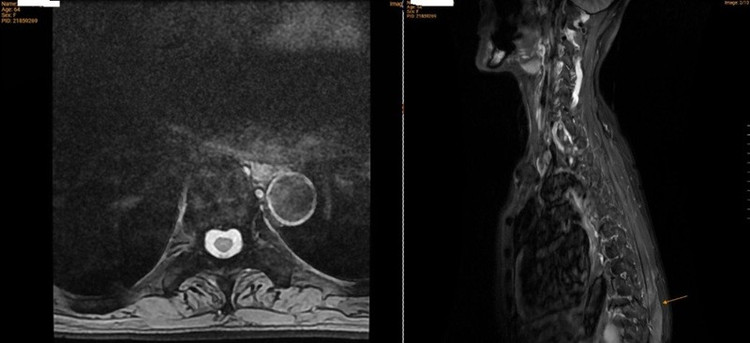

Kết quả chụp cộng hưởng từ (MRI) cột sống cho thấy, bệnh nhân có xẹp mới đốt sống L2 trên nền nhiều đốt sống xẹp mạn tính trước đó (T8, T10, T11, L4, L5), kèm theo tình trạng thoái hóa cột sống, phình và thoát vị đĩa đệm, cũng như viêm phần mềm vùng cột sống lưng – thắt lưng.

Kết quả chụp MRI của bệnh nhân ghi nhận nhiều đốt sống bị xẹp